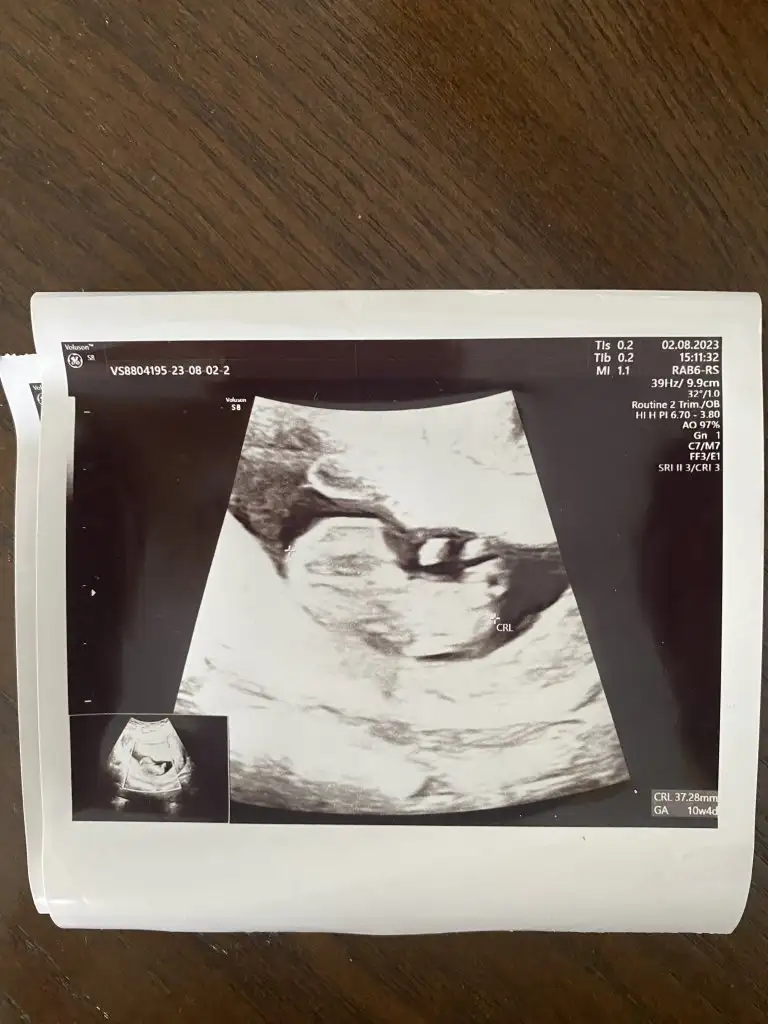

Banada tahminde bulunabılırmisiniz lütfen❤️💓💙bastakıler 9+2 sondaki 10+4